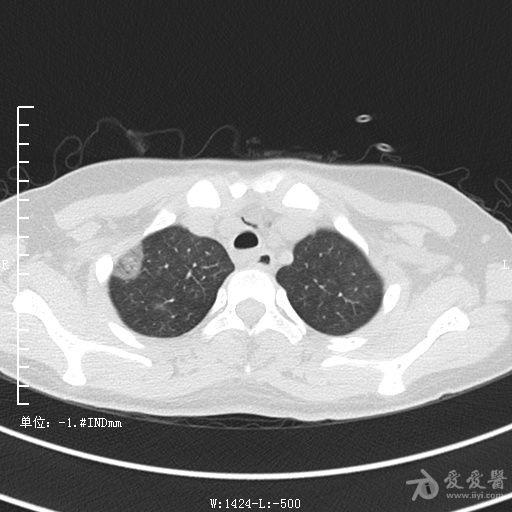

典型支气管扩张及肺水肿CT片

典型支气管扩张肺水肿